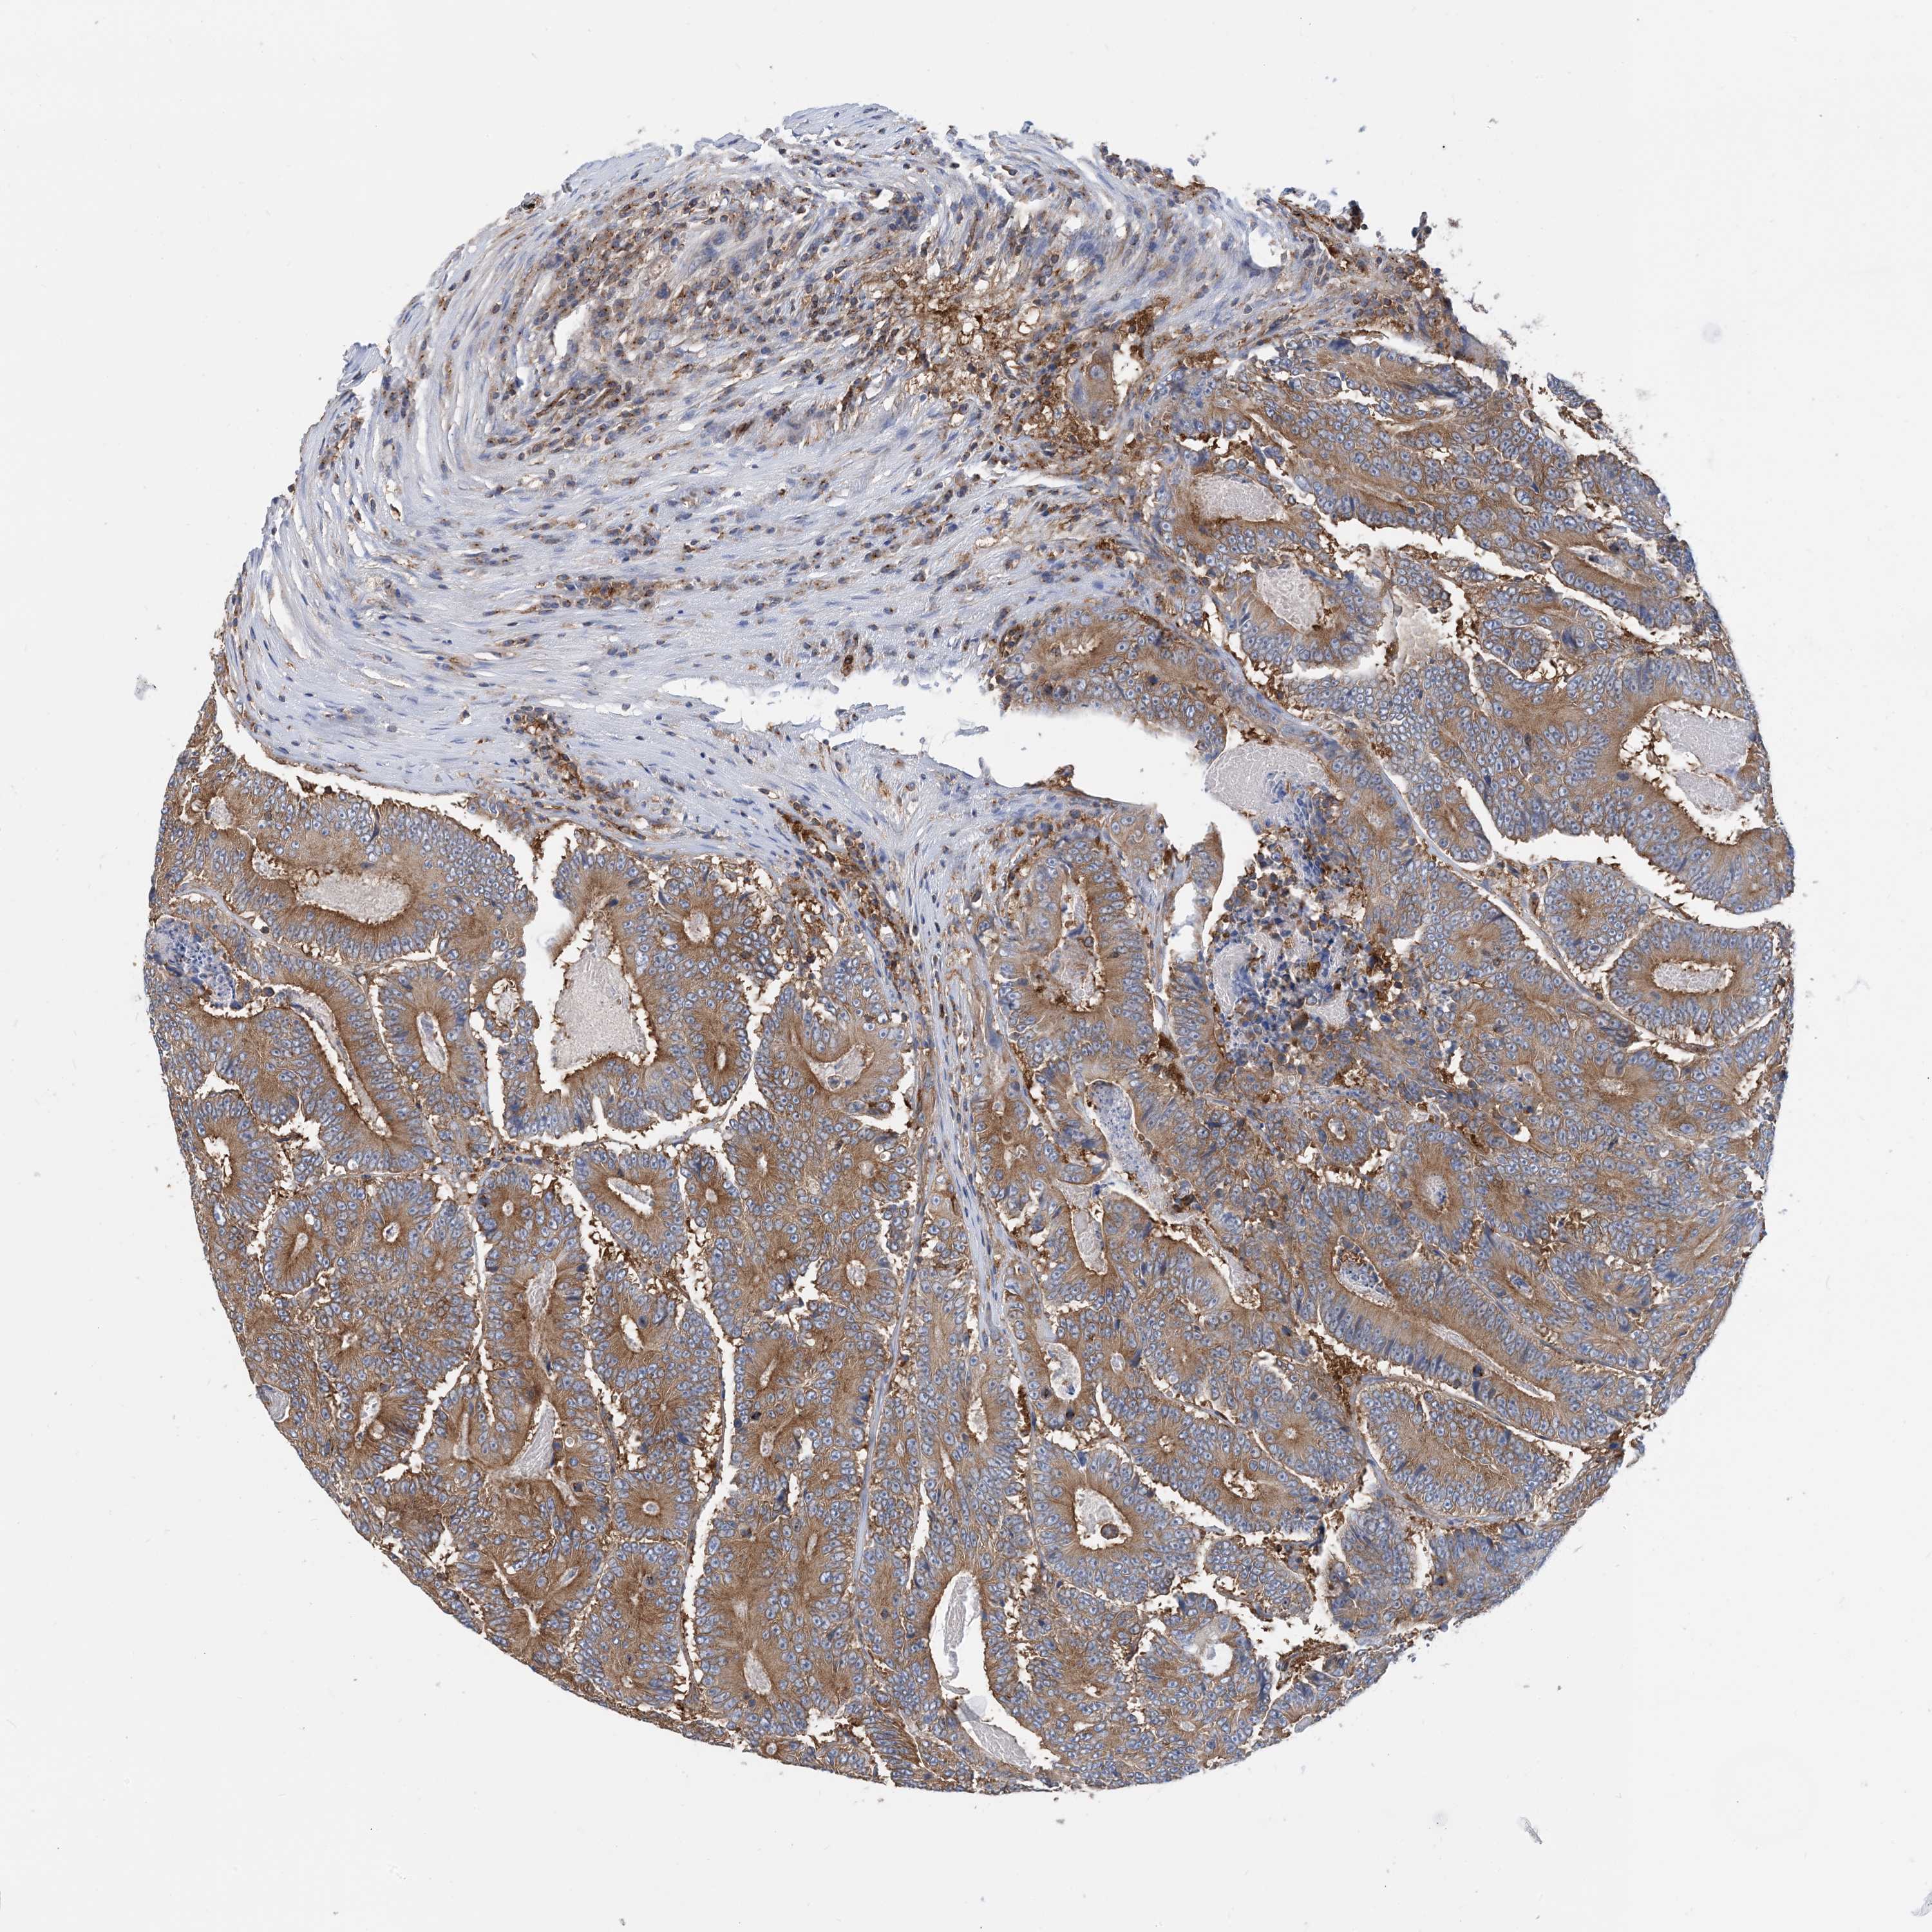

CANCER COLORECTAL CANCER Show tissue menu

Colorectal cancer

Human cancer

Colon adenocarcinoma